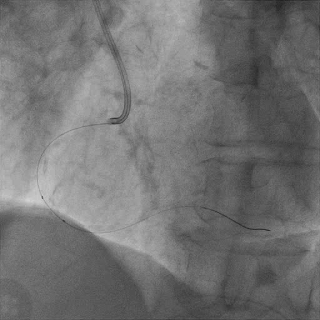

对角支送入IVUS导管,在IVUS实时指引下用尝试穿刺闭塞段

导丝未能进入闭塞段,导丝进入间隔支

逆向造影指引下继续尝试穿刺闭塞段

导丝远端与逆向造影不重叠,未在血管真腔

反复调整导丝最终进入D2#,可见导丝远端与D2侧枝重叠,证明远端位于真腔

微导管交换工作导丝至D2#远端

双腔微导管辅助下,导丝在逆向造影指引下成功通过LAD闭塞段,逆向造影显示导丝走行于LAD真腔内

交换工作导丝至LAD远端

预扩球囊依次扩张LAD近中段病变处,造影可见远端血管显影,导丝位于真腔。